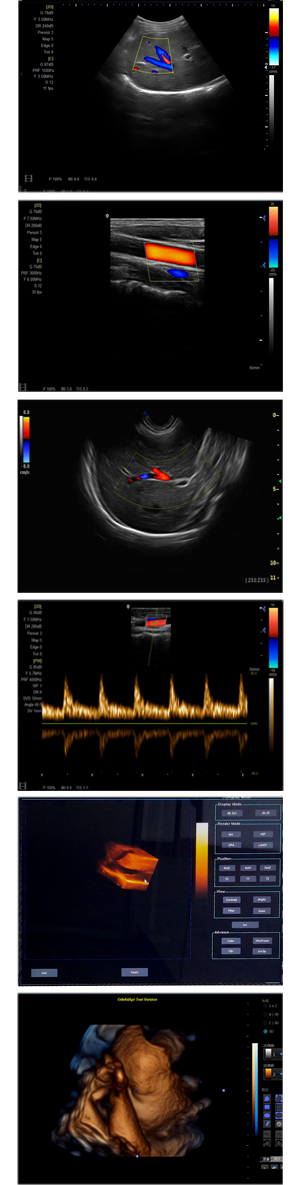

XF-7500型,秉承先鋒彩超技術(shù)之精華,擁有高雅大氣的獨(dú)特外型,為最新一代應(yīng)用型數(shù)字彩色多普勒診斷系統(tǒng),魅力與實(shí)力相融合。可廣泛適用于腹部、婦產(chǎn)科、心臟、小器官、乳腺、肌骨及外周血管等諸多方面的診查,讓您在臨床超聲診斷應(yīng)用領(lǐng)域得心應(yīng)手,綻放異彩!

● 3D/ 4D成像技術(shù)/選配

● 應(yīng)用于腹部、腎臟、泌尿系統(tǒng)、產(chǎn)科、婦科、盆腔、大動(dòng)脈、肌肉組織、小器官、乳腺、心臟等

● 能量多普勒成像(PDI)

● 彩色血流量圖(CDE)

● 脈沖頻譜多普勒成像(PW)